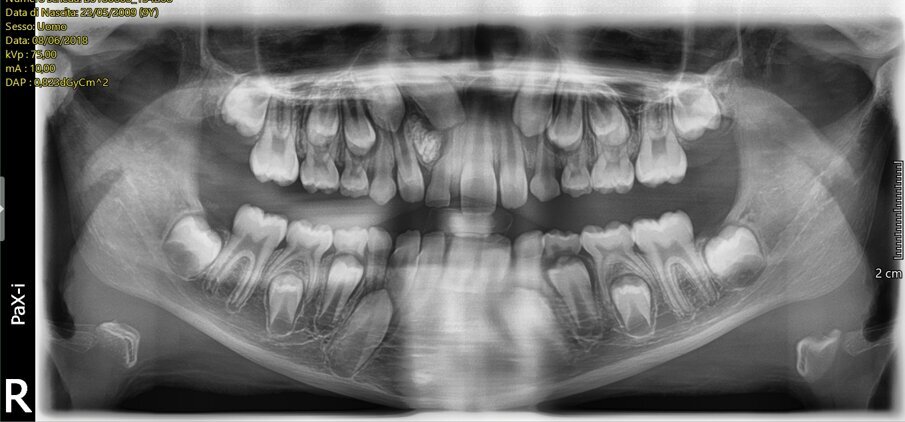

Il paziente (maschio, di anni 10) si presenta alla nostra attenzione lamentando la mancata eruzione in arcata dell’elemento 1.1 associata a una tumefazione con consistenza solida, non dolente e non dolorabile situata in corrispondenza dell’apice dell’elemento 5.1 (Fig. 1).

In seguito all’esame obiettivo e dopo aver preso visione dello studio radiografico del caso (effettuato mediante esami di 1° e 2° livello) si diagnostica la presenza di una neoformazione di dimensioni approssimativamente pari a 7,4 x 8,3 mm posizionata tra gli elementi 5.1 e 5.2 il cui aspetto è compatibile con quello di un odontoma (Figg. 2, 3). La presenza di questa neoformazione impedisce il normale tragitto eruttivo dell’elemento 1.1 che appare inoltre leggermente mesio-inclinato: questa condizione indica come terapia elettiva l’enucleazione chirurgica della massa neoformata e la contestuale cementazione di un attacco ortodontico per procedere al recupero dell’elemento ritenuto.

Fig. 2_Ortopantomografia delle arcate dentarie che evidenzia i rapporti con gli elementi dentari adiacenti.